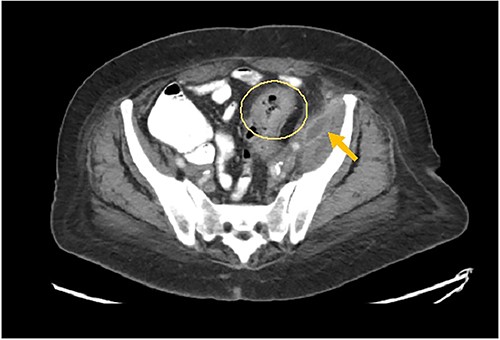

A 73-year-old female with past medical history of hypertension, diabetes mellitus, hyperlipidemia, recent history of complicated sigmoid diverticulitis with psoas abscess measuring 1.4 cm × 6.5 cm (Images 1 and 2). Patient underwent interventional radiology drain placement in the abscess cavity and antibiotic treatment with adequate response and was discharged home with oral antibiotics. Her last colonoscopy was 1 year prior, with no evidence of polyps. She followed up after 10 days with our colorectal surgeon. She denied any pain, her drain output was minimal. She was offered surgical intervention, however she refused. Drain was removed. She presented to the hospital again after 3 weeks with lower abdominal pain with radiation to left back and with anterior left upper thigh pain. She felt a sensation of fullness in that area. She was tolerating diet and having normal bowel movements. She denied any fevers, chills, urinary complaints. On the physical exam, her abdomen was soft, non-distended, there was tenderness to palpation in her left lower quadrant, no rebound, no rigidity. There was also severe tenderness to palpation in the left antero-lateral thigh. There were no skin changes, crepitus to palpation or drainage from this area.

Arrows shows extension of psoas abscess through abdominal wall in the surrounding tissues around the hip. There is not Hip bone involvement. Circle shows abscess next to the hip.